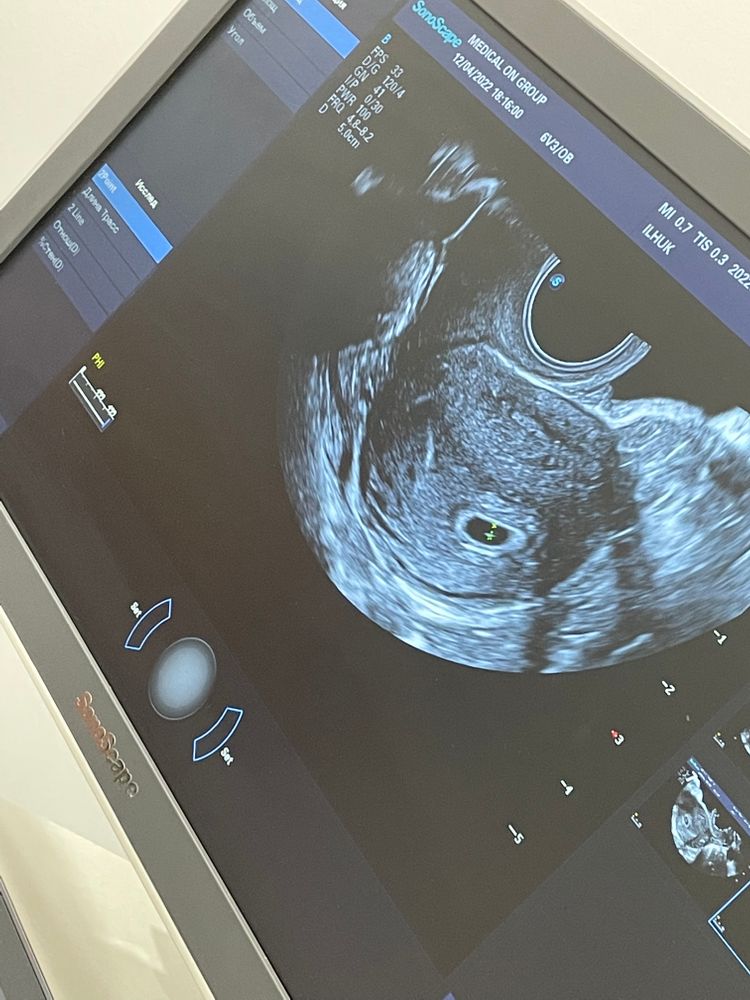

Узи и положительные тесты

История успешного зачатия6 тестов, все положительные. 12 дней задержки, электронный тест показывает беременность 3+

12.04.2022